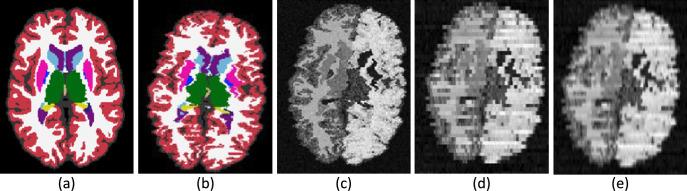

We present open-source tools for three-dimensional (3D) analysis of photographs of dissected slices of human brains, which are routinely acquired in brain banks but seldom used for quantitative analysis. Our tools can: (1) 3D reconstruct a volume from the photographs and, optionally, a surface scan; and (2) produce a high-resolution 3D segmentation into 11 brain regions per hemisphere (22 in total), independently of the slice thickness. Our tools can be used as a substitute for ex vivo magnetic resonance imaging (MRI), which requires access to an MRI scanner, ex vivo scanning expertise, and considerable financial resources. We tested our tools on synthetic and real data from two NIH Alzheimer's Disease Research Centers. The results show that our methodology yields accurate 3D reconstructions, segmentations, and volumetric measurements that are highly correlated to those from MRI. Our method also detects expected differences between confirmed Alzheimer's disease cases and controls. The tools are available in our widespread neuroimaging suite 'FreeSurfer' (https://surfer.nmr.mgh.harvard.edu/fswiki/PhotoTools).

我们提供了用于分析人脑解剖切片照片的开源工具,这些工具通常在脑库中获取,但很少用于定量分析。我们的工具可以:(1)从照片中(可选地从表面扫描中)重建体积;(2)将高分辨率的 3D 分割为每个半球的 11 个脑区(总共 22 个),而与切片厚度无关。我们的工具可以替代需要访问 MRI 扫描仪、体外扫描专业知识和大量资金的体外磁共振成像(MRI)。我们在来自两个 NIH 阿尔茨海默病研究中心的合成和真实数据上测试了我们的工具。结果表明,我们的方法产生的 3D 重建、分割和体积测量结果与 MRI 非常相关。我们的方法还检测到确认的阿尔茨海默病病例和对照组之间的预期差异。这些工具可在我们广泛使用的神经影像学套件 'FreeSurfer'(https://surfer.nmr.mgh.harvard.edu/fswiki/PhotoTools)中使用。